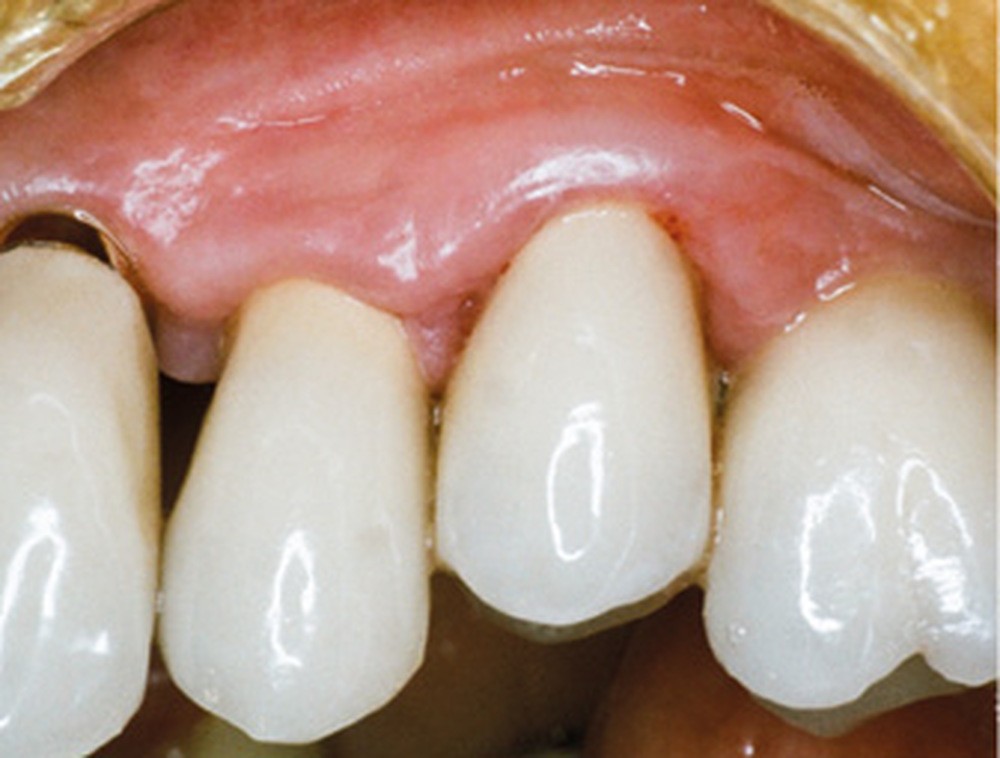

En mars 2016, la patiente se plaint d’une sensibilité sur la 25 et on note cliniquement une inflammation gingivale associée à un décalage apical du rebord marginal et de la ligne muco-gingivale en comparaison de leur situation visualisée au niveau des coiffes supra-implantaires. La couronne clinique est réduite et une infraposition avec une inocclusion d’environ 2 mm par rapport au plan d’occlusion et aux dents antagonistes est également notée (fig. 2 à 4). Un saignement au sondage ainsi qu’une poche de 5 mm en distal sont constatés. Le test de percussion est positif. Les tissus péri-implantaires adjacents ne présentent aucun signe de mucosite.